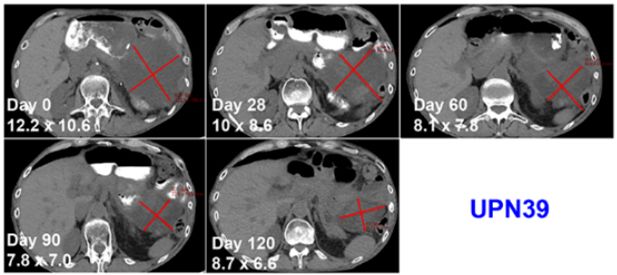

“这项试验主要关注3个问题:我们能不能用这种特别的方式编辑T细胞? 得到的T细胞还有功能吗? 这些细胞能安全回输到患者体内吗?”这项研究的主要作者、主持临床试验的Edward Stadtmauer博士表示。“数据表明,这三个问题的答案都是肯定的。”更令人欣喜的是,除了安全性得到认可之外,临床试验编号UPN39 的患者输注自体NYCE T后4个月内肿瘤持续缩小。

红色表示X肿瘤,持续缩小ing